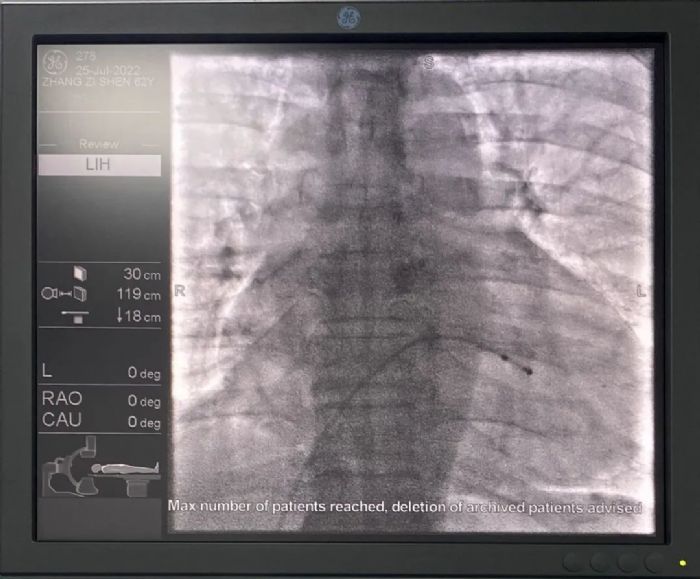

【大病不出县】精准施救,立竿见影——绥宁县人民医院成功开展首例临时心脏起搏器植入术 7月25日,绥宁县人民医院为一位交界性逸搏心律的老年男性患者,完成绥宁县首例临时心脏起搏器植入术。此例手术的成功开展,标志着绥宁县人民医院在心脏介入诊疗技术上取得了新突破。 62岁老年男性患者,因“胸闷、气促伴恶心半天”入院,入院时心率28次/分,心电图示交界性逸搏心律,有临时起搏器植入指征。 临时心脏起搏是治疗严重心律失常的一种应急和有效的措施,也是心肺复苏的急救手段,具有省时、迅速、简便的特点,应用恰当如同救命奇兵。 因患者心率过慢,低于30次/分,随时都有可能出现心跳骤停的风险,绥宁县人民医院心血管内科主任姜同辉立即将病情告知患者及家属。征得患者及家属同意后,在局麻下为患者行经股静脉临时起搏器植入术,随着起搏器的顺利植入,患者的症状明显得到改善,术后安返病房,心率为60次/分。 术后患者心率 姜同辉主任检查患者心脏起搏情况 此次临时起搏器植入术的成功开展,是绥宁县人民医院介入导管中心新技术发展的又一次重要里程碑,进一步推动了心血管介入治疗的全面开展和心血管内科诊疗技术再提升,为绥宁县及周边地区心血管病友带来了福音! |